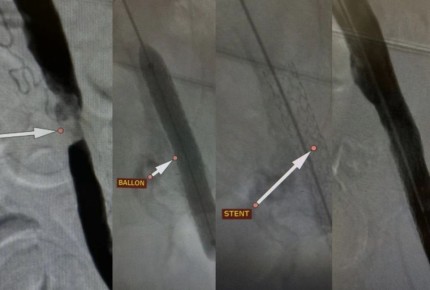

53-летний мужчина был госпитализирован с невозможностью наступать на больную конечность, сильными болями, нарушающими сон, холодностью и бледностью кожи ноги. Врачи выявили значительное сужение артерий ноги, что...